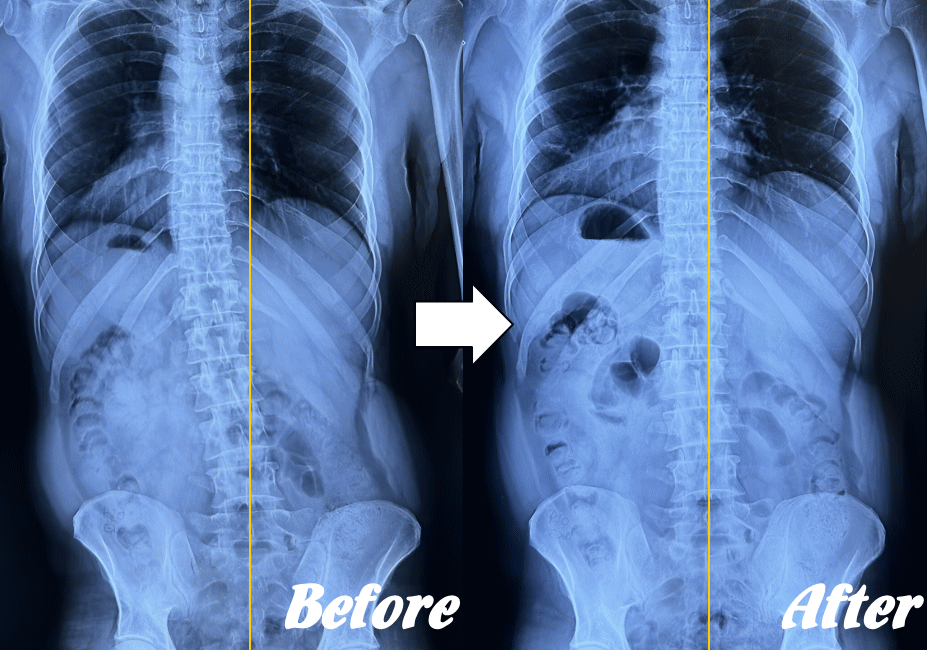

【体の整体】による変化

※ X線/MRI/CT検査画像のデータをお持ちの方はご持参いただければ当院で参考にさせていただきます。

施術前と施術後01